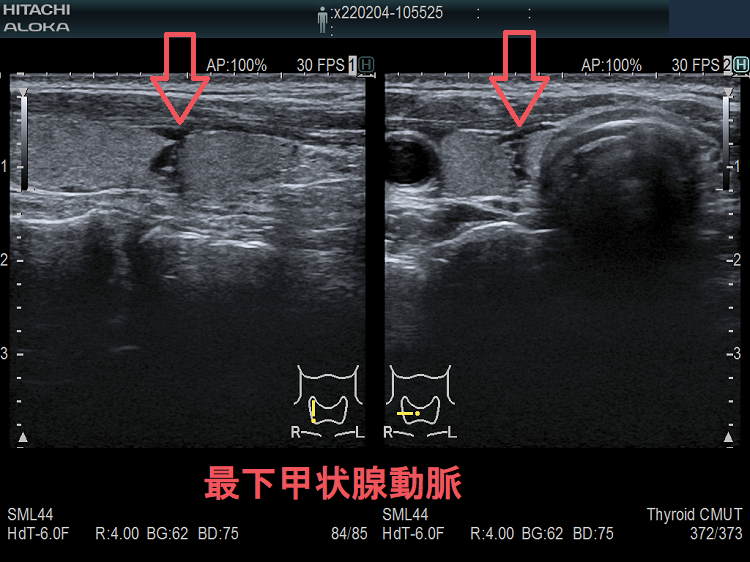

甲状腺穿刺細胞診の主な有害事象の一つは穿刺時出血、穿刺後出血;最悪、気道閉塞により窒息。注意しても唾を飲む方におこる。用手圧迫、再度、超音波エコー、造影CT、喉頭ファイバー行い出血・喉頭腫大を確認後入院。甲状腺機能亢進症/バセドウ病、TSH高値の重度甲状腺機能低下症は甲状腺内部血流が異常増加し穿刺で大出血の危険。甲状腺ホルモン正常化し血流低下を待つ。頚動脈に接する・連鎖して拍動する、下甲状腺動脈直下の小さな甲状腺腫瘍は穿刺難。甲状腺血管腫は何度穿刺細胞診しても血液成分のみで穿刺後出血の危険。最下甲状腺動脈穿刺で大出血。

- 下甲状腺動脈直下で穿刺困難の小さな甲状腺腫瘍